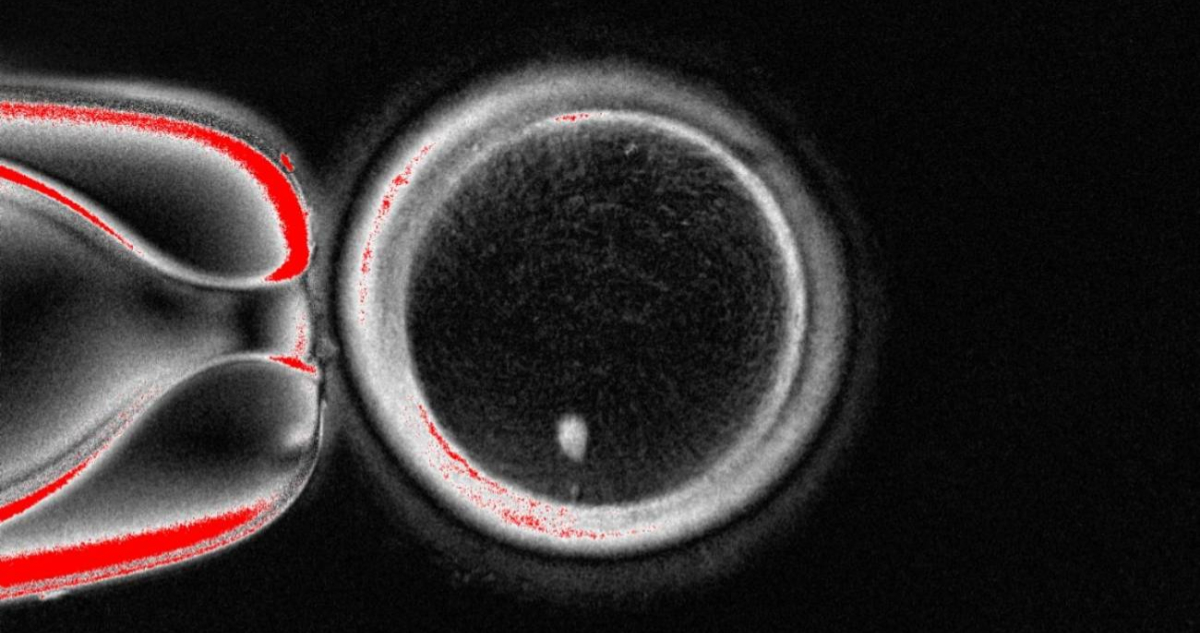

El procedimiento consiste en transferir el núcleo de una célula somática —como las de la piel— a un óvulo donado sin núcleo, y provocar que divida su carga genética, imitando los pasos de la meiosis natural.

El experimento permitió obtener 82 óvulos funcionales, que fueron fecundados con esperma humano. Un 9 % alcanzó la fase de blastocisto, correspondiente a los primeros seis días de desarrollo embrionario. Aunque ninguno se cultivó más allá de ese punto, los autores destacan que se trata de una prueba de concepto que demuestra la viabilidad de generar gametos humanos a partir de células somáticas.

“Todavía no hemos conseguido que los 23 cromosomas correctos se eliminen al formar el corpúsculo polar”, explica Martí. “Esto ocurre porque, al introducir el núcleo de una célula somática en el óvulo, los cromosomas homólogos no se alinean correctamente en el nuevo huso acromático. Al no producirse ese emparejamiento, la separación durante la división genera muchas alteraciones genéticas (aneuploidías) que impiden el desarrollo normal del embrión”, añade.